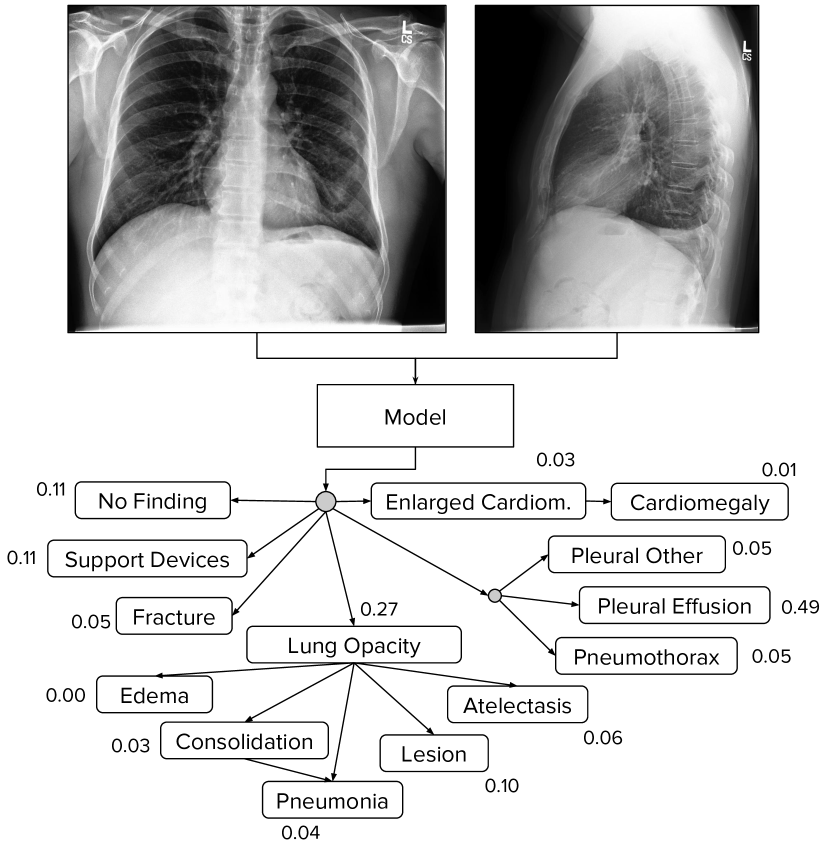

The CheXpert task is to predict the probability of 14 different observations from multi-view chest radiographs (see Figure 1). We pay particular attention to uncertainty labels in the dataset, and investigate different approaches towards incorporating those labels into the training process. We assess the performance of these uncertainty approaches on a validation set of 200 labeled studies, where ground truth is set by a consensus of 3 radiologists who annotated the set using the radiographs. We evaluate the approaches on 5 observations selected based on their clinical significance and prevalence in the dataset, and find that different uncertainty approaches are useful for different observations.

We train models that take as input a single-view chest radiograph and output the probability of each of the 14 observations. When more than one view is available, the models output the maximum probability of the observations across the views.